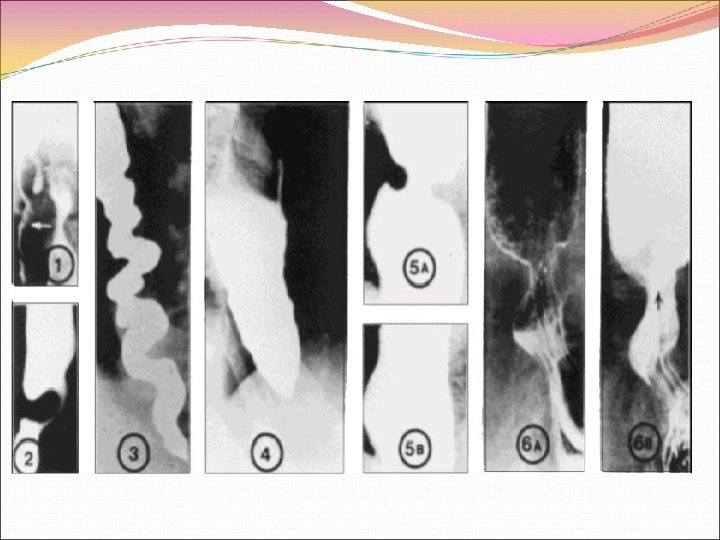

Нарушения глотания при СС обусловлены нарушениями структуры стенки и моторной функции пищевода. У больных СС гладкая мускулатура нижней трети пищевода замещается коллагеном. Поперечно полосатая мускулатура верхней трети пищевода обычно не поражается. Возникает стеноз нижних отделов пищевода и компенсаторное расширение верхних. Изменяется структура слизистой пищевода – метаплазия Беретта. Вследствие гастроэзофагального рефлюкса часто возникает эрозивный рефлюкс-эзофагит, развиваются язвы пищевода, постязвенные стриктуры пищеводно желудочного соустья. Возможны атония и дилятация желудка, двенадцатиперстной кишки. При возникновении диффузного фиброза желудка может нарушаться всасывание железа с формированием сидеропениического синдрома. Нередко развивается атония, дилатация тонкой кишки. Фиброз стенки тонкой кишки проявляется синдромом мальабсорбции. Поражение толстой кишки приводит к дивертикулезу, проявляется запорами.

Поражение желудочно-кишечного тракта В качестве общих рекомендаций показано дробное питание, сон на кровати с приподнятым головным концом, нежелательно ложиться в течение 2 х часов после приема пищи, нужно отказаться от приема жирной пищи, курения и приема алкоголя. Медикаментозная терапия включает в себя применение антисекреторных препаратов и прокинетиков. 1. При желудочно пищеводном рефлюксе, ГЭРБ, язвах и стриктурах пищевода применяют антисекреторные препараты, в первую очередь ингибиторы протонной помпы (омепразол 20 40 мг). Блокаторы протоновой помпы эффективнее снижают кислотность желудочного сока и уменьшают проявления ГЭРБ, в сравнении с применением блокаторов H 2 гистаминовых рецепторов.

При нарушении моторики ЖКТ (дисфагия, ГЭРБ, ранее насыщение, отрыжка, псевдо обструкция и др. ) назначают различные прокинетики метоклопрамид, домперидон, которые увеличивают давление нижнего пищеводного сфинктера, ускоряют эвакуацию содержимого из желудка и увеличивают перистальтику тонкого кишечника. От назначения цизаприда (стимулятора освобождения ацетилхолина в межмышечных нейронных сплетениях ЖКТ за счет активации серотониновых 5 HT 4 — рецепторов) практически отказались из за кардиотоксичности (в частности, удлинения интервала QT). Прокинетический эффект имеет и эритромицин, применение которого в дозе 100 150 мг 2 раза в день или азитромицина по 400 мг 1 раза в день в течение 4 недель уменьшает тошноту, рвоту и приступов болей в эпигастральной области. Комбинация прокинетиков и антисекреторных препаратов улучшает состояние пациентов с рефлюкс эзофагитом. 3. При развитии синдрома мальабсорбции, обусловленного избыточным бактериальном ростом, показано поведение антибиотикотерапии.